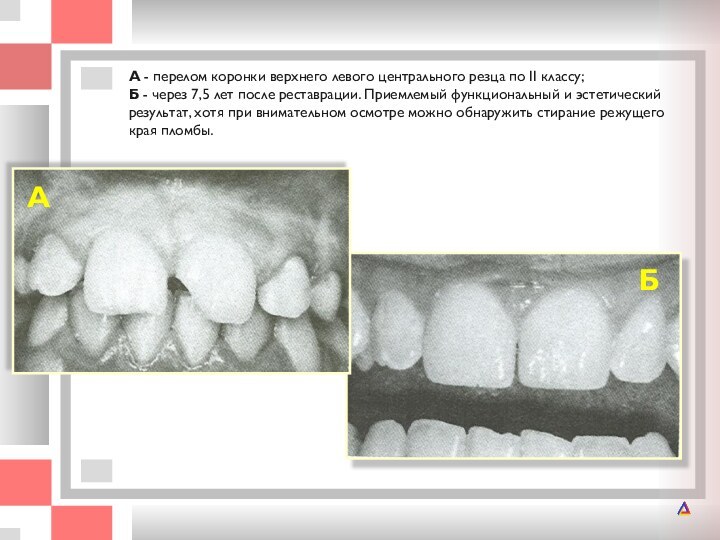

А - перелом коронки верхнего левого центрального резца по II классу;

по II классу; Б - через 7,5 лет после реставрации.

Приемлемый функциональный и эстетический результат, хотя при внимательном осмотре можно обнаружить стирание режущего края пломбы.